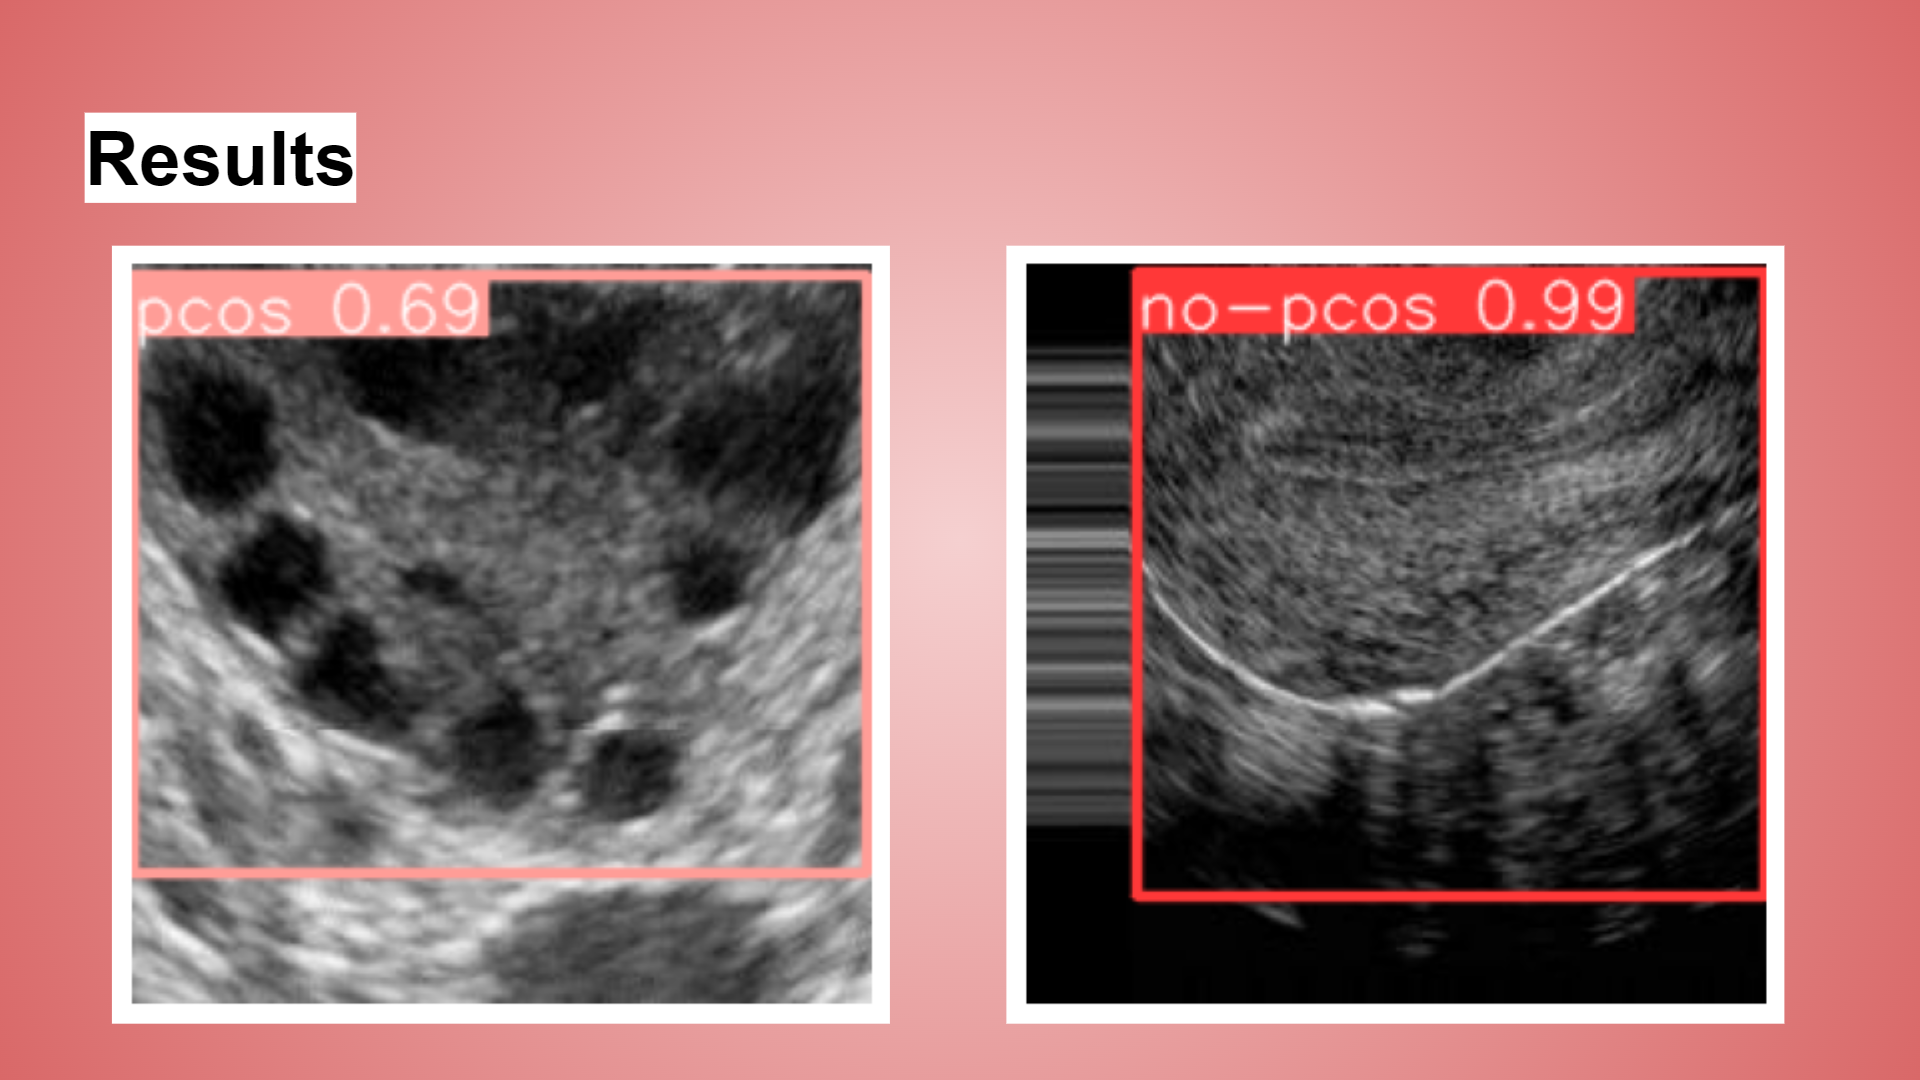

FemOvaAI is an advanced AI-driven system designed to detect Polycystic Ovarian Syndrome (PCOS) from ultrasound images. Utilizing the power of YOLOv8, a cutting-edge object detection model, our system analyzes images to classify them into two categories: "PCOS" and "No PCOS." This enables healthcare professionals to make informed decisions quickly, enhancing the diagnostic process and potentially improving patient outcomes.

Evaluation and Testing: After training, the model was evaluated on the test set to assess its accuracy, precision, recall, and overall performance. Fine-tuning was performed to optimize the model further. Achieved a test accuracy of 92.9%.